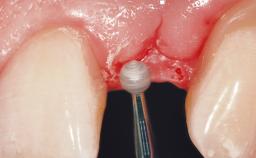

The patient presented with root fracture of the right central incisor with associated distal bone loss. After sectioning and extraction of the fractured root the distal papilla was lost, creating an esthetic compromise. This case demonstrates an option for treating this esthetic compromise. Early (Type 2) implant placement was performed at 7 weeks with simultaneous horizontal and vertical augmentation using Bio-Oss and Bio-Gide (Geistlich). After 3 months a connective tissue graft was performed at the time of implant exposure. Despite these surgical procedures, the papilla could not be recovered. As a result, a prosthetic solution was necessary.